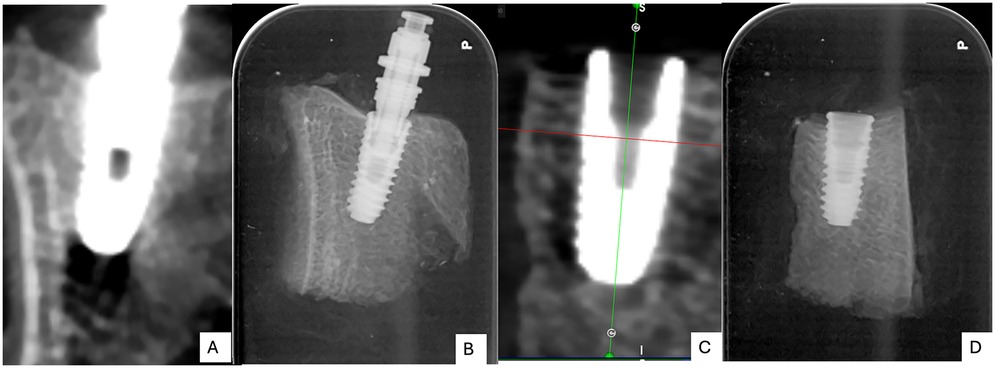

4.3 Cone beam CT and x-ray tomographic findings

The Cone beam computed tomography (CBCT) and periapical radiographs revealed differences in the bone–implant interface characteristics between the two groups. In OD group (Figures 3A,B) exhibited greater peri-implant bone densification and enhanced bone-to-implant contact when compared to the SD group (Figures 3C,D). The peri-implant bone appeared more compact and organized, especially along the apical and mid-thread zones. There was minimal radiolucency at the bone–implant interface, indicating improved bone adaptation and initial stability. In contrast, the SD group displayed a less compact trabecular structure surrounding the implant body. The SD group exhibited conventional bone-implant interface patterns typical of standard drilling protocols in Type IV bone, characterized by visible spaces between implant threads and the surrounding bone walls. The trabecular bone pattern remained unchanged from the pre-drilling architecture, confirming the non-condensing nature of standard drilling technique.

Four-panel X-ray images showing dental implants within the jawbone. Panel A: 3D view of an implant. Panel B: 2D view with implant threads visible. Panel C: D view of an implant. Panel D: 2D view with implant threads visible, but with less distinct thread detail.

Figure 3. Post-operative cone-beam computed tomography (CBCT) images (A,C) and periapical radiographs (B,D) of the two groups: osseodensification (OD; A,B) and standard drilling (SD; C,D).